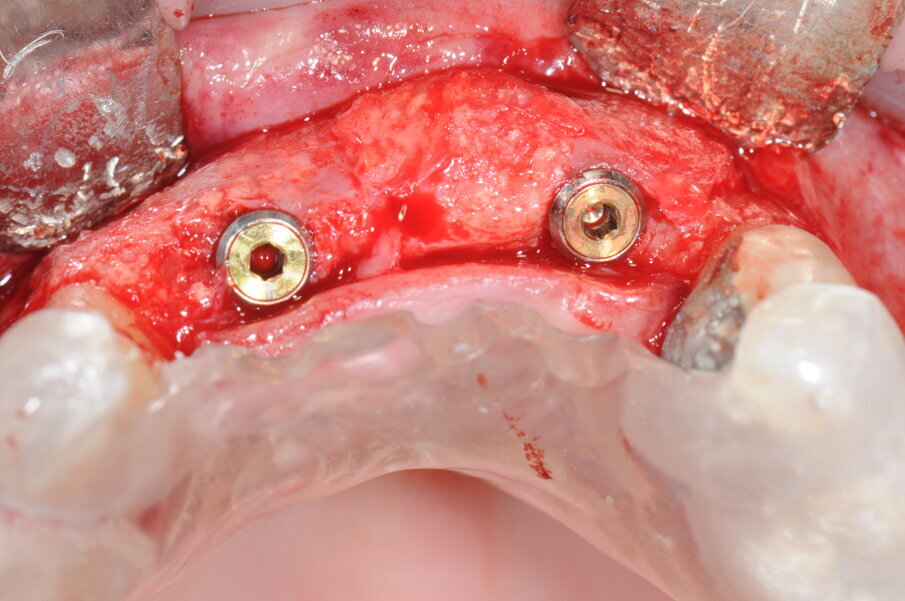

A 9 mesi è stata effettuata la seconda fase chirurgica in cui era prevista la rimozione delle viti di osteosintesi e il posizionamento degli impianti nei siti 1.1 e 1.2 (Blossomâ Intra-Lock System Europa). Grazie al volume osseo rigenerato risultava adeguato il posizionamento degli impianti come da progettazione protesica iniziale (Figg. 16-19).

Fig. 16 - Esposizione del sito rigenerato in visione occlusale.

Fig. 17 - Preparazione del sito implantare; impianti Blossom Intra-Lock.

Fig. 18 - Posizionamento delle viti tappo.

Fig. 19 - Sutura del lembo.